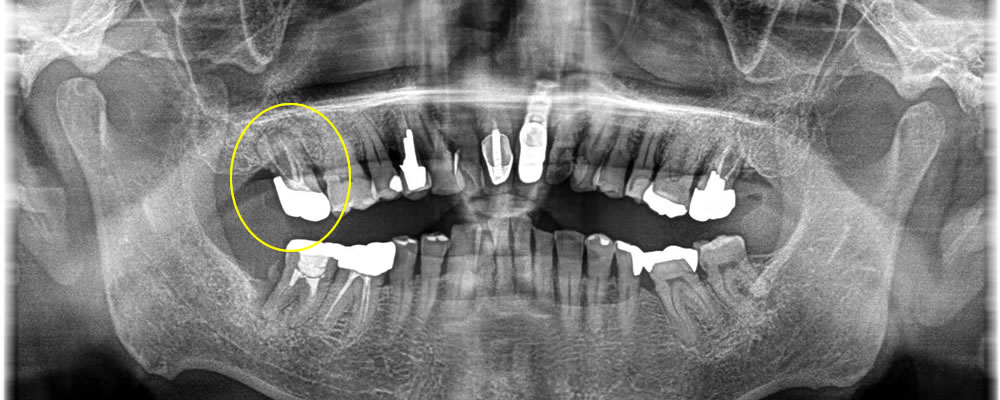

保存不可能な歯を抜歯後にインプラントで治療した症例

こちらの患者さまは他院にて左上の奥歯を残す事ができないという事でインプラント治療の説明があったが、症例の多い当院にて行いたいとの事でご来院いただきました。

まずCT写真を撮って検査を行いました。現状を確認してカウンセリングを行った上でやはりインプラント治療を行っていきたいとの事となり、オペを行いました。